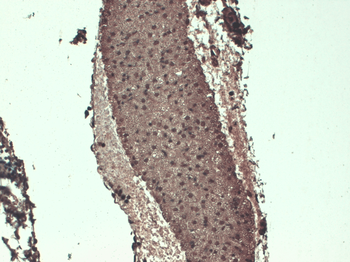

应用稀释比例:WB (1:1000), IHC (1:1000)

应用注释:1 µg/ml of SMC-391 was sufficient for detection of hNIS in 20 µg of transfected COS-7 cell membrane lysate by ECL immunoblot analysis using Goat anti-mouse IgG:HRP as the secondary antibody.